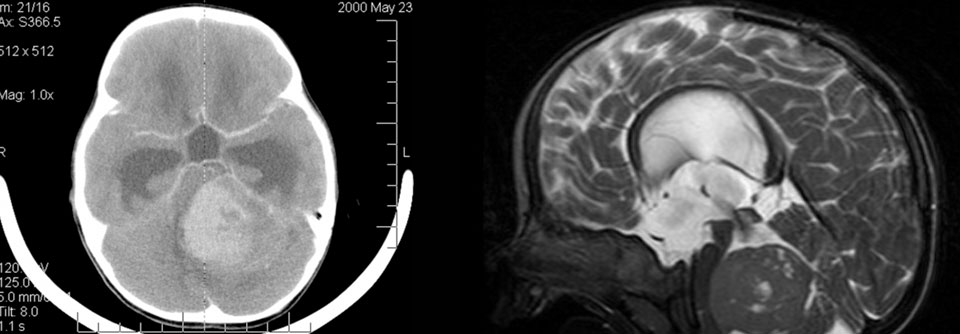

Im SRS-Mikroskop kann man gesundes Gewebe (links) gut vom Tumor (rechts) unterscheiden.

Im SRS-Mikroskop kann man gesundes Gewebe (links) gut vom Tumor (rechts) unterscheiden. © University of Michigan

Bei der SRS-Technologie gibt das Spektrum des reflektierten Lichts – die Raman-Streuung – Aufschluss darüber, ob es sich um dichtes Tumorgewebe oder gesunde Hirnsubstanz handelt. Das…